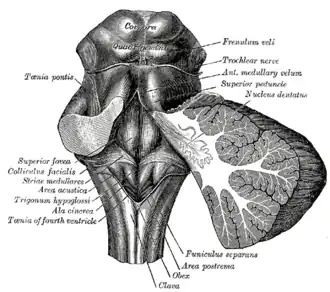

Rhomboid fossa. (Locus coeruleus not labeled, but is just lateral to the facial colliculus, which is labeled at center left.) | |

The locus coeruleus (LC) is located in the posterior area of the rostral pons in the lateral floor of the fourth ventricle. It is composed of mostly medium-size neurons. Melanin granules inside the neurons contribute to its blue colour. Thus, it is also known as the blue nucleus, or the nucleus pigmentosus pontis (heavily pigmented pontine nucleus).[5] The neuromelanin is formed by the polymerization of norepinephrine and is analogous to the black dopamine-based neuromelanin in the substantia nigra.